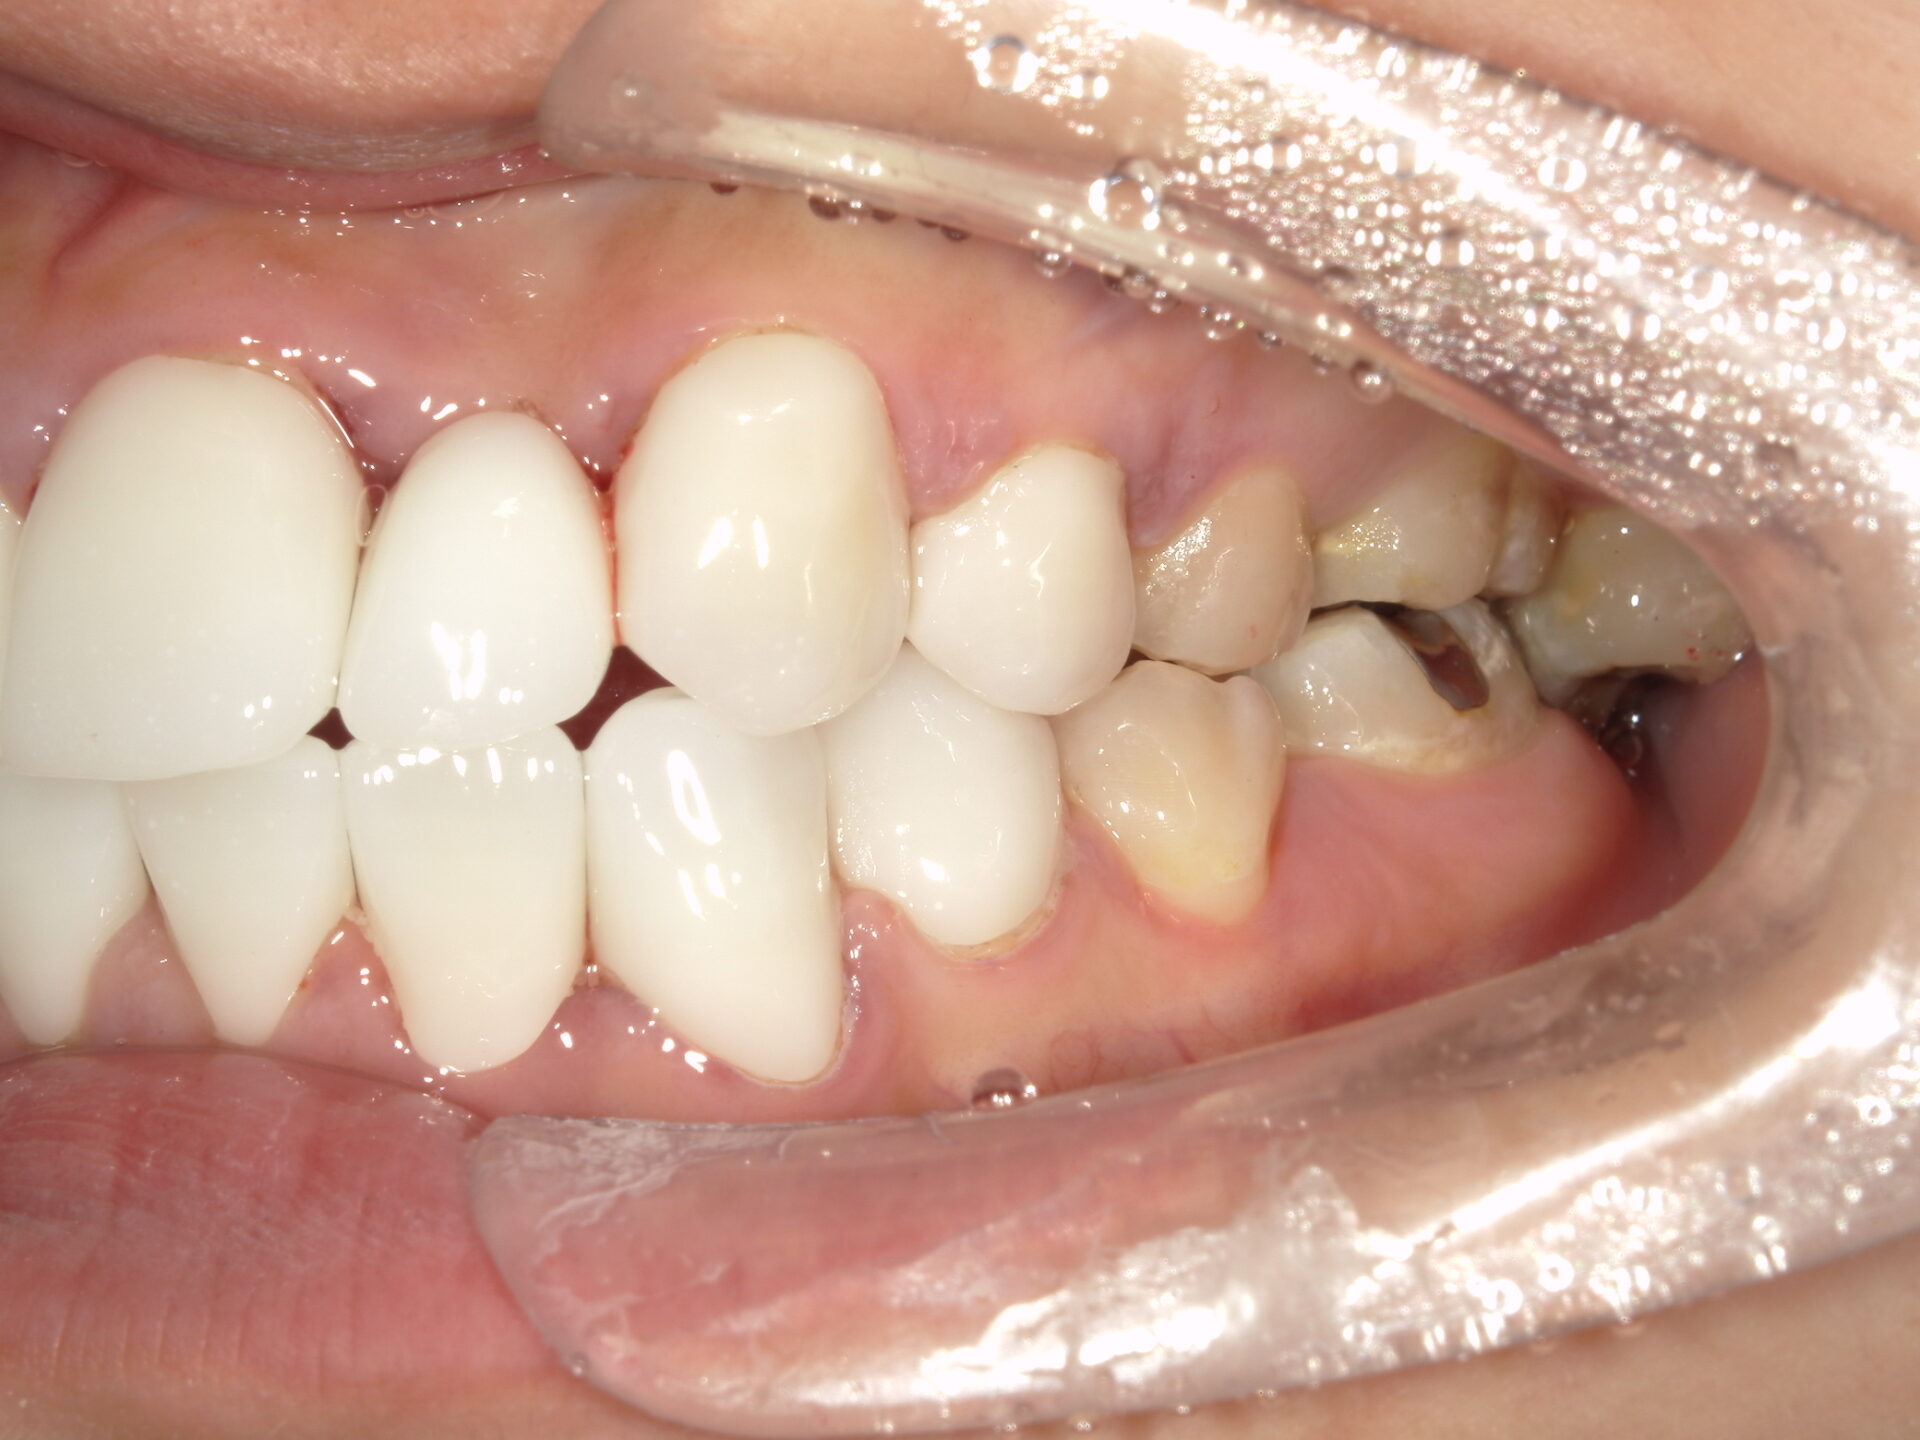

患者さんの年齢 20代 女性 症状 八重歯がコンプレックス、白い歯を入れたい 治療内容 セラミック治療 費用 費用150万(税抜) 治療期間・回数 治療期間1ヶ月・通院回数3回 メリット 治療期間・回数が少ない デメリット・リスク 術後知覚過敏が起こる事ある - セラミック治療